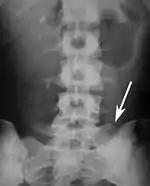

Several congenital block vertebrae in the transition from the thoracic to the lumbar spine and hemivertebrae.

Congenital block vertebra in the lumbar spine (partial vertebrae 3 and 4). The rear portion of the disc still exists.